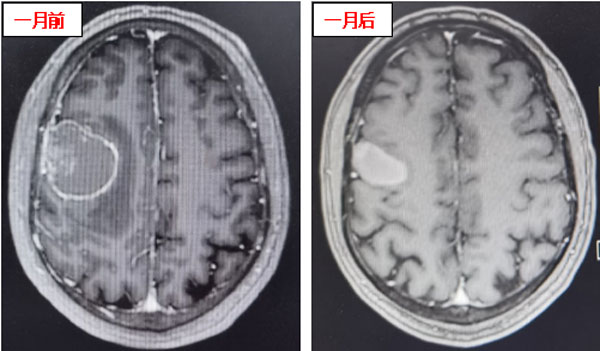

该患者为一名52岁男性,在2年前因发现右肺上叶大细胞神经内分泌癌接受手术治疗。近日,他在日常活动中突发癫痫、意识丧失而跌倒。头颅核磁显示:右额顶叶转移瘤伴瘤卒中及瘤周水肿。患者头痛明显,癫痫时有发作,左侧肢体肌力仅为3级。经过我院内科治疗后,患者头痛有所减轻,但肌力未见恢复,频繁出现口角及肢体抽搐。

患者在接受3次射波刀治疗后,头痛症状明显减轻,癫痫症状消失,肢体肌力明显好转。接受治疗1个月后,患者肢体肌力恢复正常,未再出现口角、肢体抽搐及头痛、头晕等症状,仅左侧手指尖偶有麻木感。复查头颅核磁显示:颅内病灶明显缩小,周围无明显水肿坏死征象,安全性良好,这意味着射波刀治疗成功遏制了颅内转移瘤。